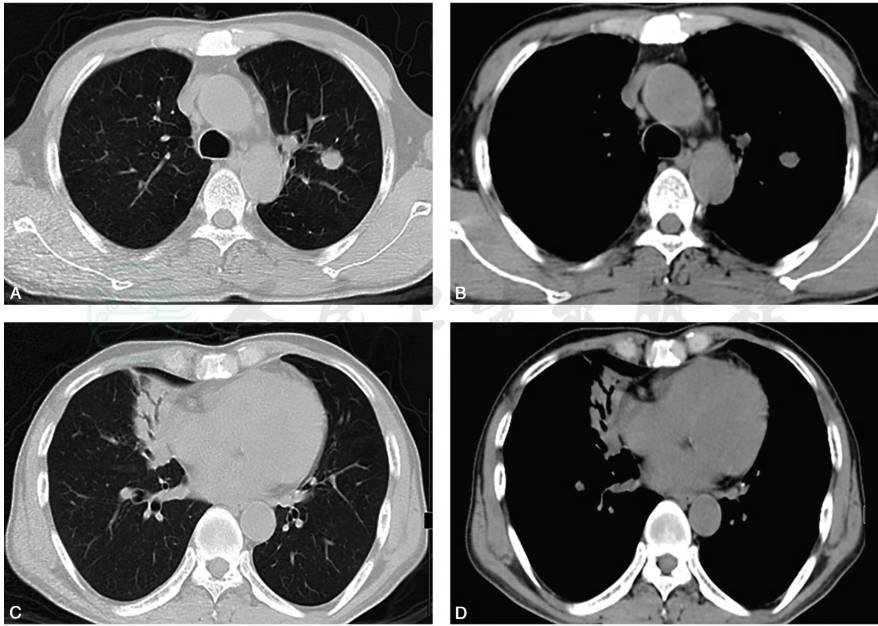

患者予青霉素治疗2天后,患者咳嗽、咳痰症状好转,体温恢复正常。治疗一周后血培养未生长细菌;血常规:白细胞:12.32×109/L,中性粒细胞:79%。查体:双肺呼吸音稍粗,未闻及干、湿性啰音。3个月后复查胸部CT:右肺中叶高密度影已基本吸收,右上肺结节明显吸收变小(图3)。

图3 胸部CT随访:青霉素治疗后3个月胸部CT(B)显示较治疗前(A)病灶已基本吸收消散